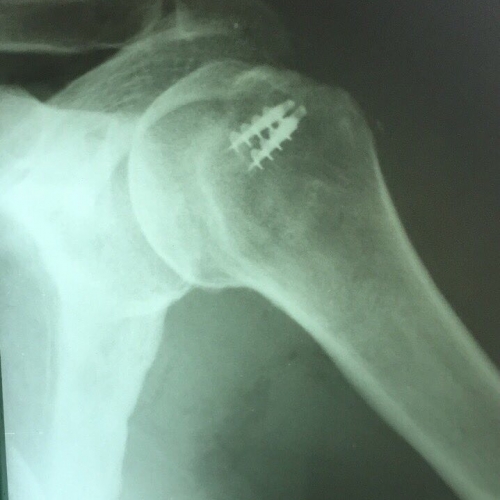

Восстановление сухожилий ротатороной манжеты плеча